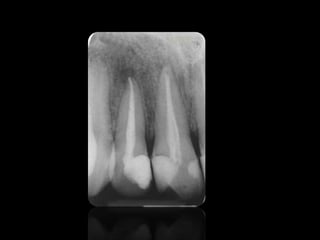

CARIES